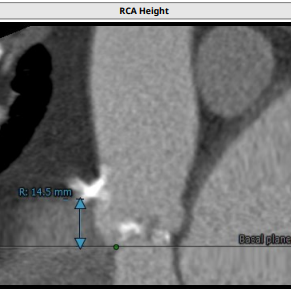

左冠高度:10.6mm,右冠高度:14.5mm。